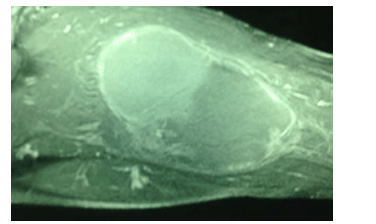

A imagem a seguir, de uma RNM da coxa direita, representa uma massa de crescimento rápido no grupo muscular posterior de um paciente do sexo masculino, negro, com lesões umbilicadas em tronco e membros superiores e inferiores. Chama a atenção a presença de uma mancha do tipo “café com leite”no ombro esquerdo. A biópsia incisional dessa lesão revelou “neoplasia fusiforme de padrão sarcomatóide; provavelmente se trata de um rabdomiossarcoma“.

A respeito desse caso clínico e da doença genética que predispõe ao surgimento da neoplasia, julgue os itens a seguir.